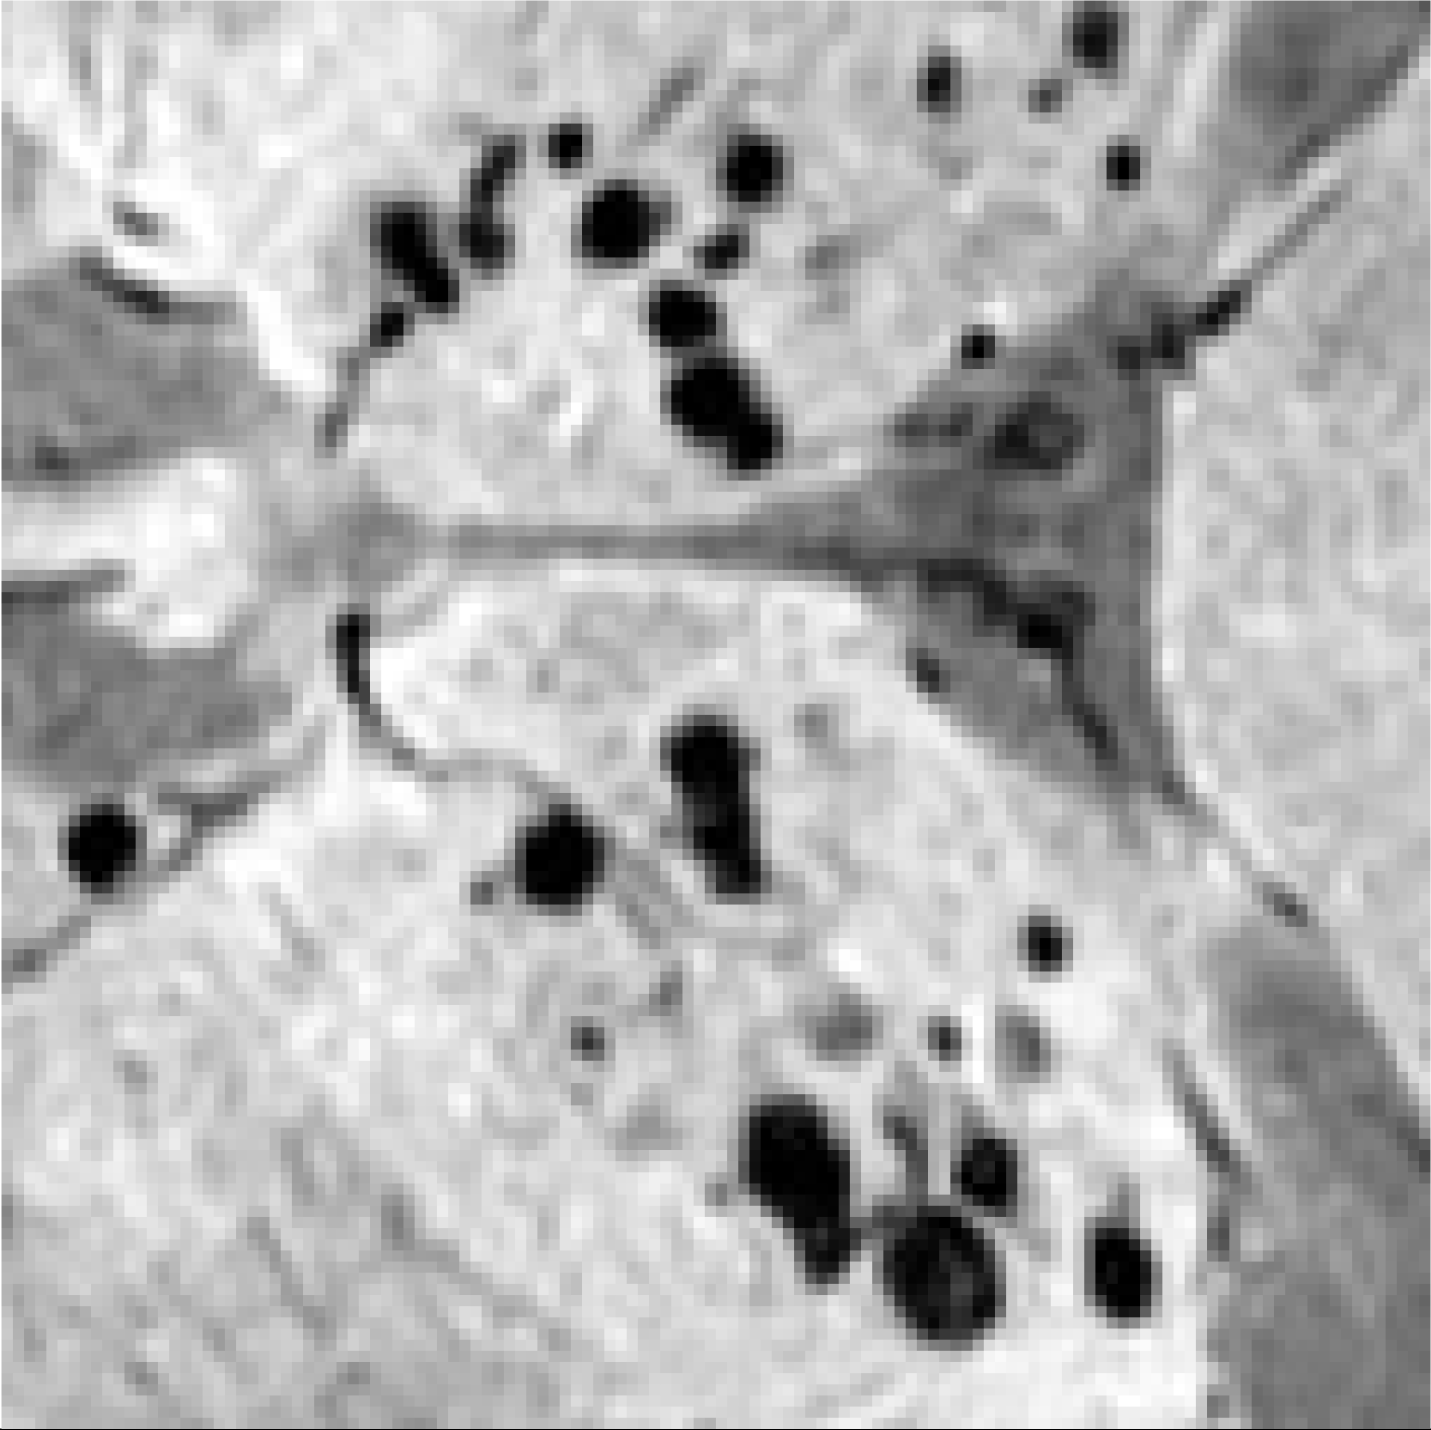

| Image | Enlarged View | Age | Gender | Lifestyle Habits | Medical History | Clinical Diagnostic Results | Our Results | |

|---|---|---|---|---|---|---|---|---|

| Patient 1 | ![]() | ![]() | 53 | Female | CADASIL | CMBs | Not CMBs | |

| Patient 2 | ![]() | ![]() | 55 | Male | Drinking and Smoking | Hypertension | CMBs | Not CMBs |

| Patient 3 | ![]() | ![]() | 78 | Male | Cerebral Calcification (Not CMBs) | CMBs |